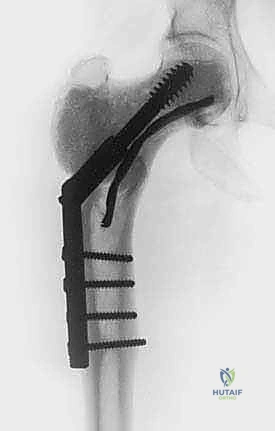

Because of this profound biomechanical degradation, prophylactic internal fixation and robust defect reconstruction are almost universally required. The cavity is typically filled with polymethylmethacrylate (PMMA) bone cement, which provides immediate structural stability, acts as a secondary thermal adjuvant during its exothermic polymerization phase, and provides a radiopaque background for detecting future radiolucent recurrences. If the subchondral bone plate is exceedingly thin (less than 3-5 mm), the heat of the PMMA and the cold of the cryogen can cause full-thickness cartilage necrosis and joint collapse. In such cases, a composite reconstruction using a layer of structural bone graft adjacent to the joint surface, backed by PMMA and internal fixation (plates and screws or intramedullary nails), is biomechanically necessary to span the defect and bypass the stress risers.

Templating is the next critical phase. Using our advanced imaging, we must digitally or physically template the planned cortical window. We determine the exact dimensions required to access the farthest reaches of the tumor cavity with our curettes and burrs. Simultaneously, we must template the hardware placement for the prophylactic reconstruction—selecting the appropriate plates, screws, or intramedullary devices that will bypass the stress riser of our window and the ablated bone segment. Anticipating the volume of PMMA or structural bone graft required is also done at this stage.

Intraoperative fluoroscopy and clinical images confirming the placement of robust internal fixation spanning the reconstructed defect.

Final radiographic verification of the reconstruction, demonstrating excellent alignment, hardware placement, and complete filling of the defect.

Despite meticulous technique, cryosurgical ablation carries a distinct and significant complication profile. As academic surgeons, we must counsel our patients transparently and be prepared to manage these complex sequelae. The most common and devastating complication is a postoperative pathological fracture. The incidence of fracture ranges from 5% to 15%, depending heavily on the anatomical location, the size of the cortical window, and the adequacy of prophylactic fixation. The profound thermal necrosis weakens the bone significantly, and the necrotic phase peaks between 4 to 8 weeks postoperatively, making this the highest-risk window for structural failure. Salvage management for a fracture typically involves revision open reduction and internal fixation (ORIF), often requiring longer spanning plates, structural allografts, or in severe cases of joint collapse, conversion to a megaprosthesis or total joint arthroplasty.